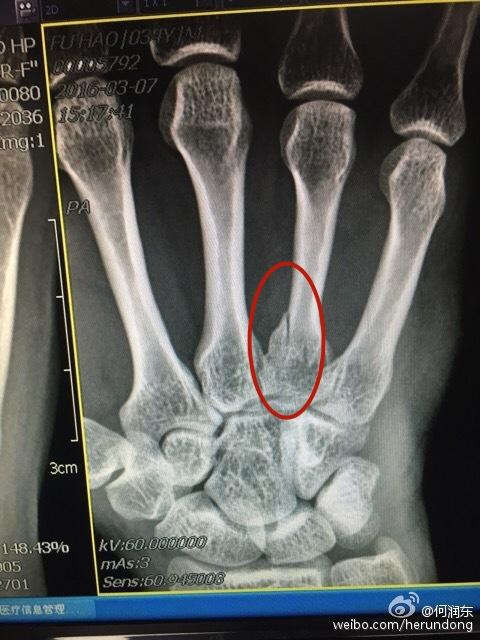

他晒了两张手掌的X光片,确实伤得还蛮重,手背上一根骨头完全骨折,痕迹相当清晰,只是看看也能硬生生地感到疼啊。

无论怎么看何润东这次的受伤都要比2016年严重得多,那次也是右手,X光片显示无名指有个地方的骨头裂开了,裹了厚厚的石膏,三个星期的时间基本就好完了。